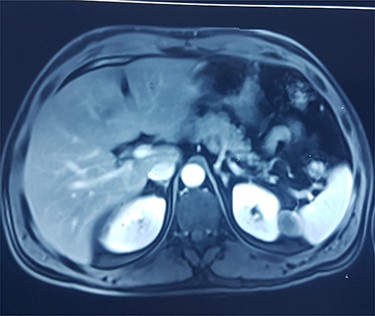

This is a 50-year-old patient with a history of medically treated renal lithiasis, who consults for left low back pain. The patient was apyretic and reported no urinary symptoms. The clinical examination was without any particularities. There was no organomegaly or lumbar contact on bimanual palpation. Biologically, there were no abnormalities, including no biological inflammatory syndrome, and renal function was preserved. The urine culture was sterile. Renal ultrasound revealed a 3-cm left cortical renal mass with moderate vascuarization. Abdominal CT scan confirmed the presence of a heterogeneous Bosniak type 3 cystic mass having a thickened wall (Fig. 1). Abdominal MRI showed a left polar cyst having an exophytic development and a thickened wall with spontaneous T2 hypointensity and T1 hyperintensity without any pathological enhancement after Gadolinium injection (Fig. 2). The retained diagnosis was an hemorrhagic benign cyst. At multidisciplinary meeting, the decision was to perform an MRI 3 months later which showed a left medio-renal cortical cystic mass measuring 24 × 28 mm having a T1 hyperintensity and heterogeneous T2 hypointensity, with a thickened wall mildly enhanced after contrast injection evoking a Bosniak type-3 hemorrhagic cyst. Seeing the MRI results, we decided to perform a left tumorectomy. Pre-operatively, the perirenal tissues were inflammatory and adherent to the capsule, a complete dissection of the kidney was performed allowing the identification of the tumor which was of a 3-cm diameter and a partially exophyctic development, then we cut the tumor with a 2-mm surgical margin. No urinary tract leakage was observed. Finally, renorraphy was performed in two plans using Vicryl 2-0 and 1 (Ethicon, Cincinnati, OH, USA). After confirming the lack of active bleeding, we placed a drainage tube and closed the incision. The total operation time was 1 h 45 min, with 18 min of selective clamping. The post-operative course was uneventful, and the patient was discharged 2 days post-operatively. The histopathological examination revealed a 2.5 × 2.7 cm necrotic lesion with an inflammatory interstitial infiltrate dissociating the epithelial structures (Fig. 3). The retained diagnosis was a pseudo tumoral Xanthogranulomatous pyelonephritis. The CT performed 3-months after surgery showed no abnormalities.

CT showing a heterogeneous Bosniak type-3 cystic mass having a thickened wall.